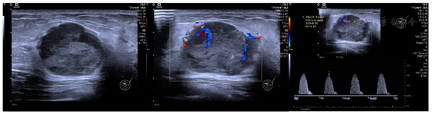

灰阶超声及多普勒超声提示:左侧乳腺10点方向,距乳头3 cm处探及大小为30.0 mm×24.4 mm的椭圆形、低回声结节,结节边界清楚,形态欠规则,部分边缘呈微分叶,内部回声不均匀,后方可见回声增强;CDFI示结节周边及内部可见条索状及点棒状血流信号,Adler分级2级,RI=0.81(图1)。

高频超声是乳腺肿块首选的影像学检查手段,根据病灶不同的组织病理学类型,其声像图表现各异。典型的髓样癌是MCB中最常见的类型,组织病理学表现为[5]:①具有低分化肿瘤细胞的合胞体生长模式,占肿瘤组织≥75%;②间质中有广泛而显著的淋巴浆细胞浸润;③肿瘤组织内无腺体或脂肪性乳腺组织;④低倍镜下肿瘤组织边界清楚,外周有纤维结构。因此,髓样癌的超声征象表现为边界清楚的不均质低回声结节。由于肿瘤内部间质成分少,声束透声好,结节后方可出现回声增强;当肿瘤较大时,局部可发生出血、坏死、囊性变,表现为结节内部散在的小片状或不规则液性暗区[6]。

乳腺纤维腺瘤的灰阶超声征象与MCB有重叠,二者时常难以鉴别。而联合多普勒超声、弹性成像及超声造影可以有效提高超声诊断的特异性。大部分MCB的血供较为丰富,Adler血流2-3级,表现为高阻力指数(RI>0.7)动脉频谱[7],与纤维腺瘤有着较为明显的区别(Adler血流0-1级,低阻力指数动脉频谱)。但多普勒超声反映的血流信号以及阻力指数与超声仪器、超声医师的操作手法有关,存在一定的主观性。而超声造影则可通过显示造影剂微泡的运动、分布,定量反映病灶区域的微循环血流灌注。髓样癌的超声造影表现为边界清晰、均匀的强化和较高的平均峰强度值,提示其存在丰富的血供[8]。此外,超声弹性成像通过反映病灶的硬度,在一定程度上有助于良恶性病灶的鉴别诊断。但既往研究发现弹性成像对MCB的鉴别存在一定争议。有研究认为MCB的弹性成像评分与纤维腺瘤无显著差异[7],而另一部分研究者则认为由于MCB周边存在纤维结构,其周边硬度较大,与纤维腺瘤有显著的差异[9]。故弹性成像在鉴别MCB中的应用仍需进一步研究。

回顾本病例,患者于洗澡时意外发现乳腺肿块,未诉特殊不适,查体时未见乳房皮肤有显著改变;病灶的灰阶超声征象与纤维腺瘤极为相似,但多普勒超声提示结节Adler血流2级(RI=0.81),超声造影呈现不均匀的向心高增强模式也进一步反映病灶丰富的血供,可与纤维腺瘤相鉴别;而MCB弹性成像提示结节质地中等,无显著的硬环征,则无法与纤维腺瘤区别。和大部分乳腺癌一样,MCB起病隐匿,临床症状不明显,易被患者忽略,以致错过治疗良机。故而应加大乳腺癌相关知识的科普,鼓励患者自查,定期体检。发现乳腺肿块后,首选超声进行筛查,辅以多普勒超声、弹性成像、超声造影可以提高诊断的特异性。此外,部分MCB血流稀少,质地中等或偏软,与良性病灶无法鉴别,为减少误诊率,必要时应行超声引导下穿刺活检以明确诊断。